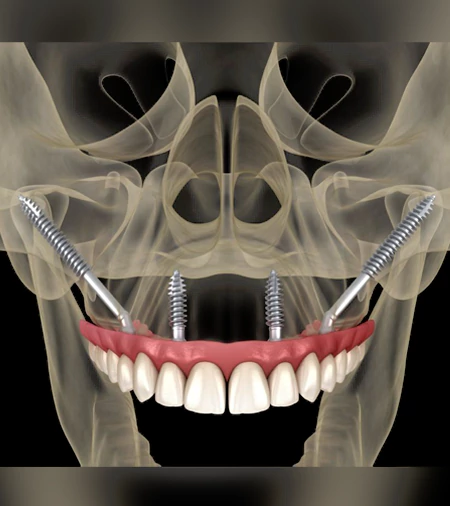

Yes, the installation of zygomatic implants by the Stella Technique is a Russian roulette. Perhaps you were lucky in your first cases where you followed the "success recipe" and had an excellent bone anchorage of the zygomatic implant in the body of the zygoma. However, randomness and probability will sooner or later be expressed, and you will install the zygomatic implant too far or even dangerously out of the ideal position, despite having strictly followed the technique. If you believe that t

Computer-Guided Approach for Placement of Zygomatic Implants

Straumann zygomatic implants for the quad zygoma procedure